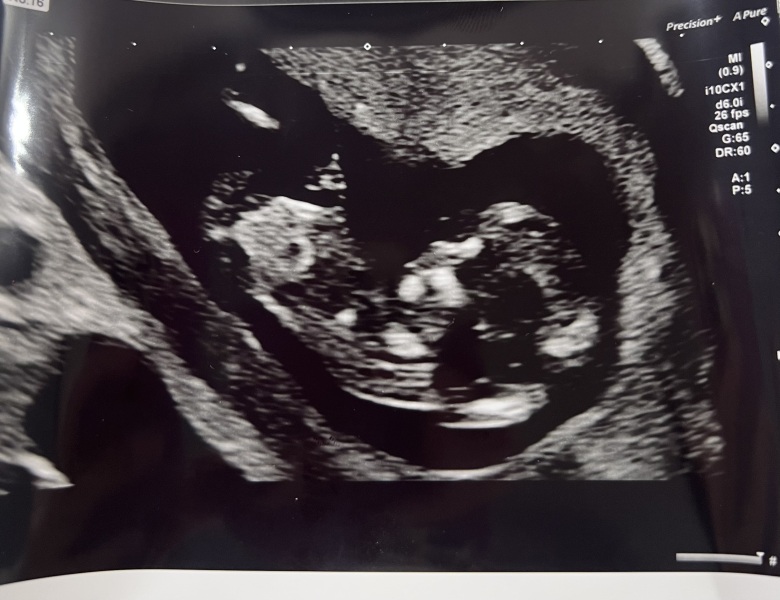

Hi based on this 12 weeks scan would you say boy or girl?

Boy! Angle from nub to spinal line is >30°. Congrats.